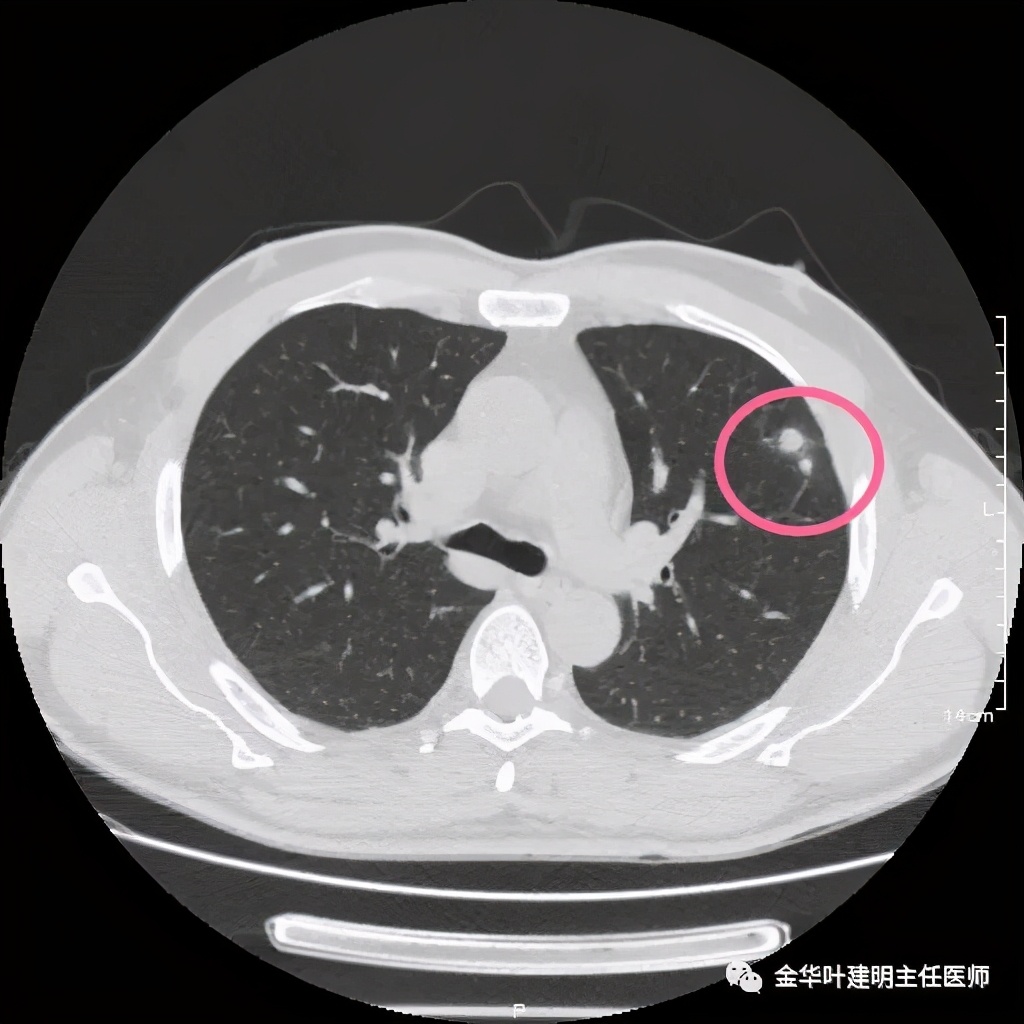

患者为48岁男性,检查发现左肺上叶实性结节,临床没有炎症表现,肿瘤指标不高,没有查过结核及隐球菌荚膜抗原试验或G试验、M试验等。我们先来看其前一个月时的平扫影像:

上图示有血管征,与病灶关系较密切

上图示血管与病灶临近,但没有被病灶牵拉从而进入病灶

我们见左上实性病灶,主病灶旁有卫星灶,有血管进入,但也有贴边走行,边缘略显模糊,膨胀感与细毛刺不明显,收缩力也不明显。下面是其靶扫描的片子: